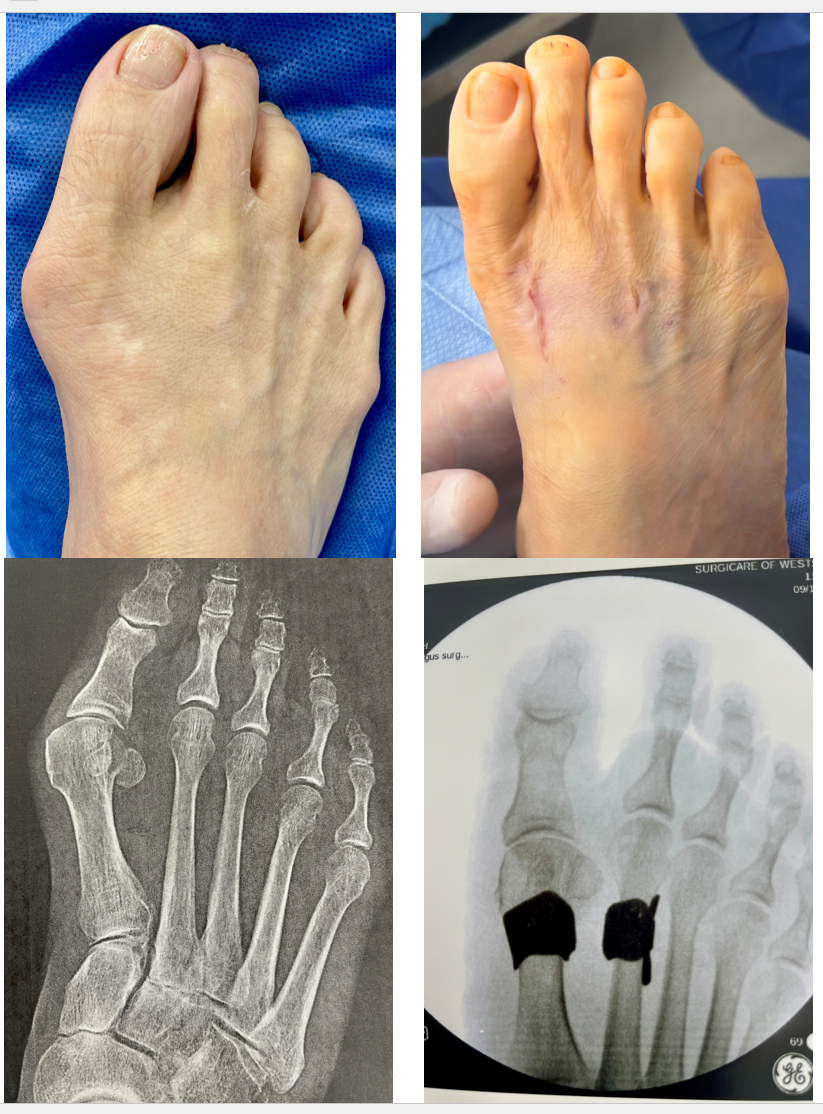

Bio: The patient is a 67-year-old woman from Ulster County, NY, who lives an active and healthy lifestyle. She had endured painful bunions for more than six years. Orthotics, specialty shoes, and medications brought no relief, and she wasn’t willing to undergo traditional surgery as it is too invasive with too much recovery time.

Procedure: HyperFlex®️ provided a new option for correcting her bunion as it is a minimally invasive, bone-preserving solution that corrects bunion deformity by addressing the soft tissue imbalance at its source.

Result: As seen in the pre- and post-operative images and x-rays, the HyperFlex®️ procedure was able to correct her bunion in less than an hour with only a small incision along the first metatarsal, and no removal of bone was necessary.